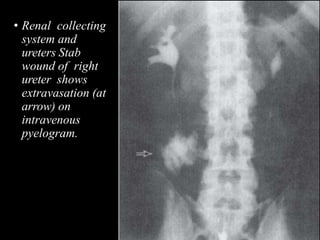

• Renal collecting

system and

ureters Stab

wound of right

ureter shows

extravasation (at

arrow) on

intravenous

pyelogram.